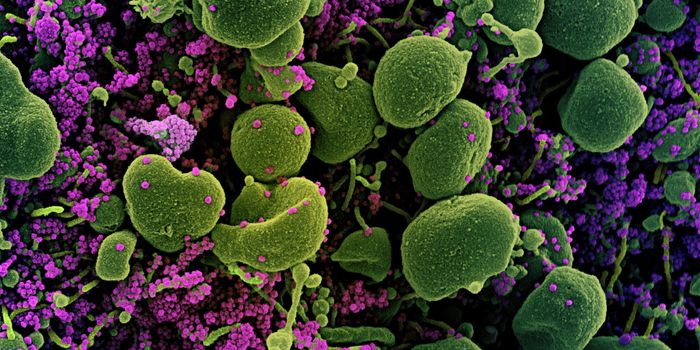

SEP 25, 2021Health & MedicineAfter a year-long study, researchers have assembled a detailed narrative about how the SARS-Cov-2 virus has spread on th ...